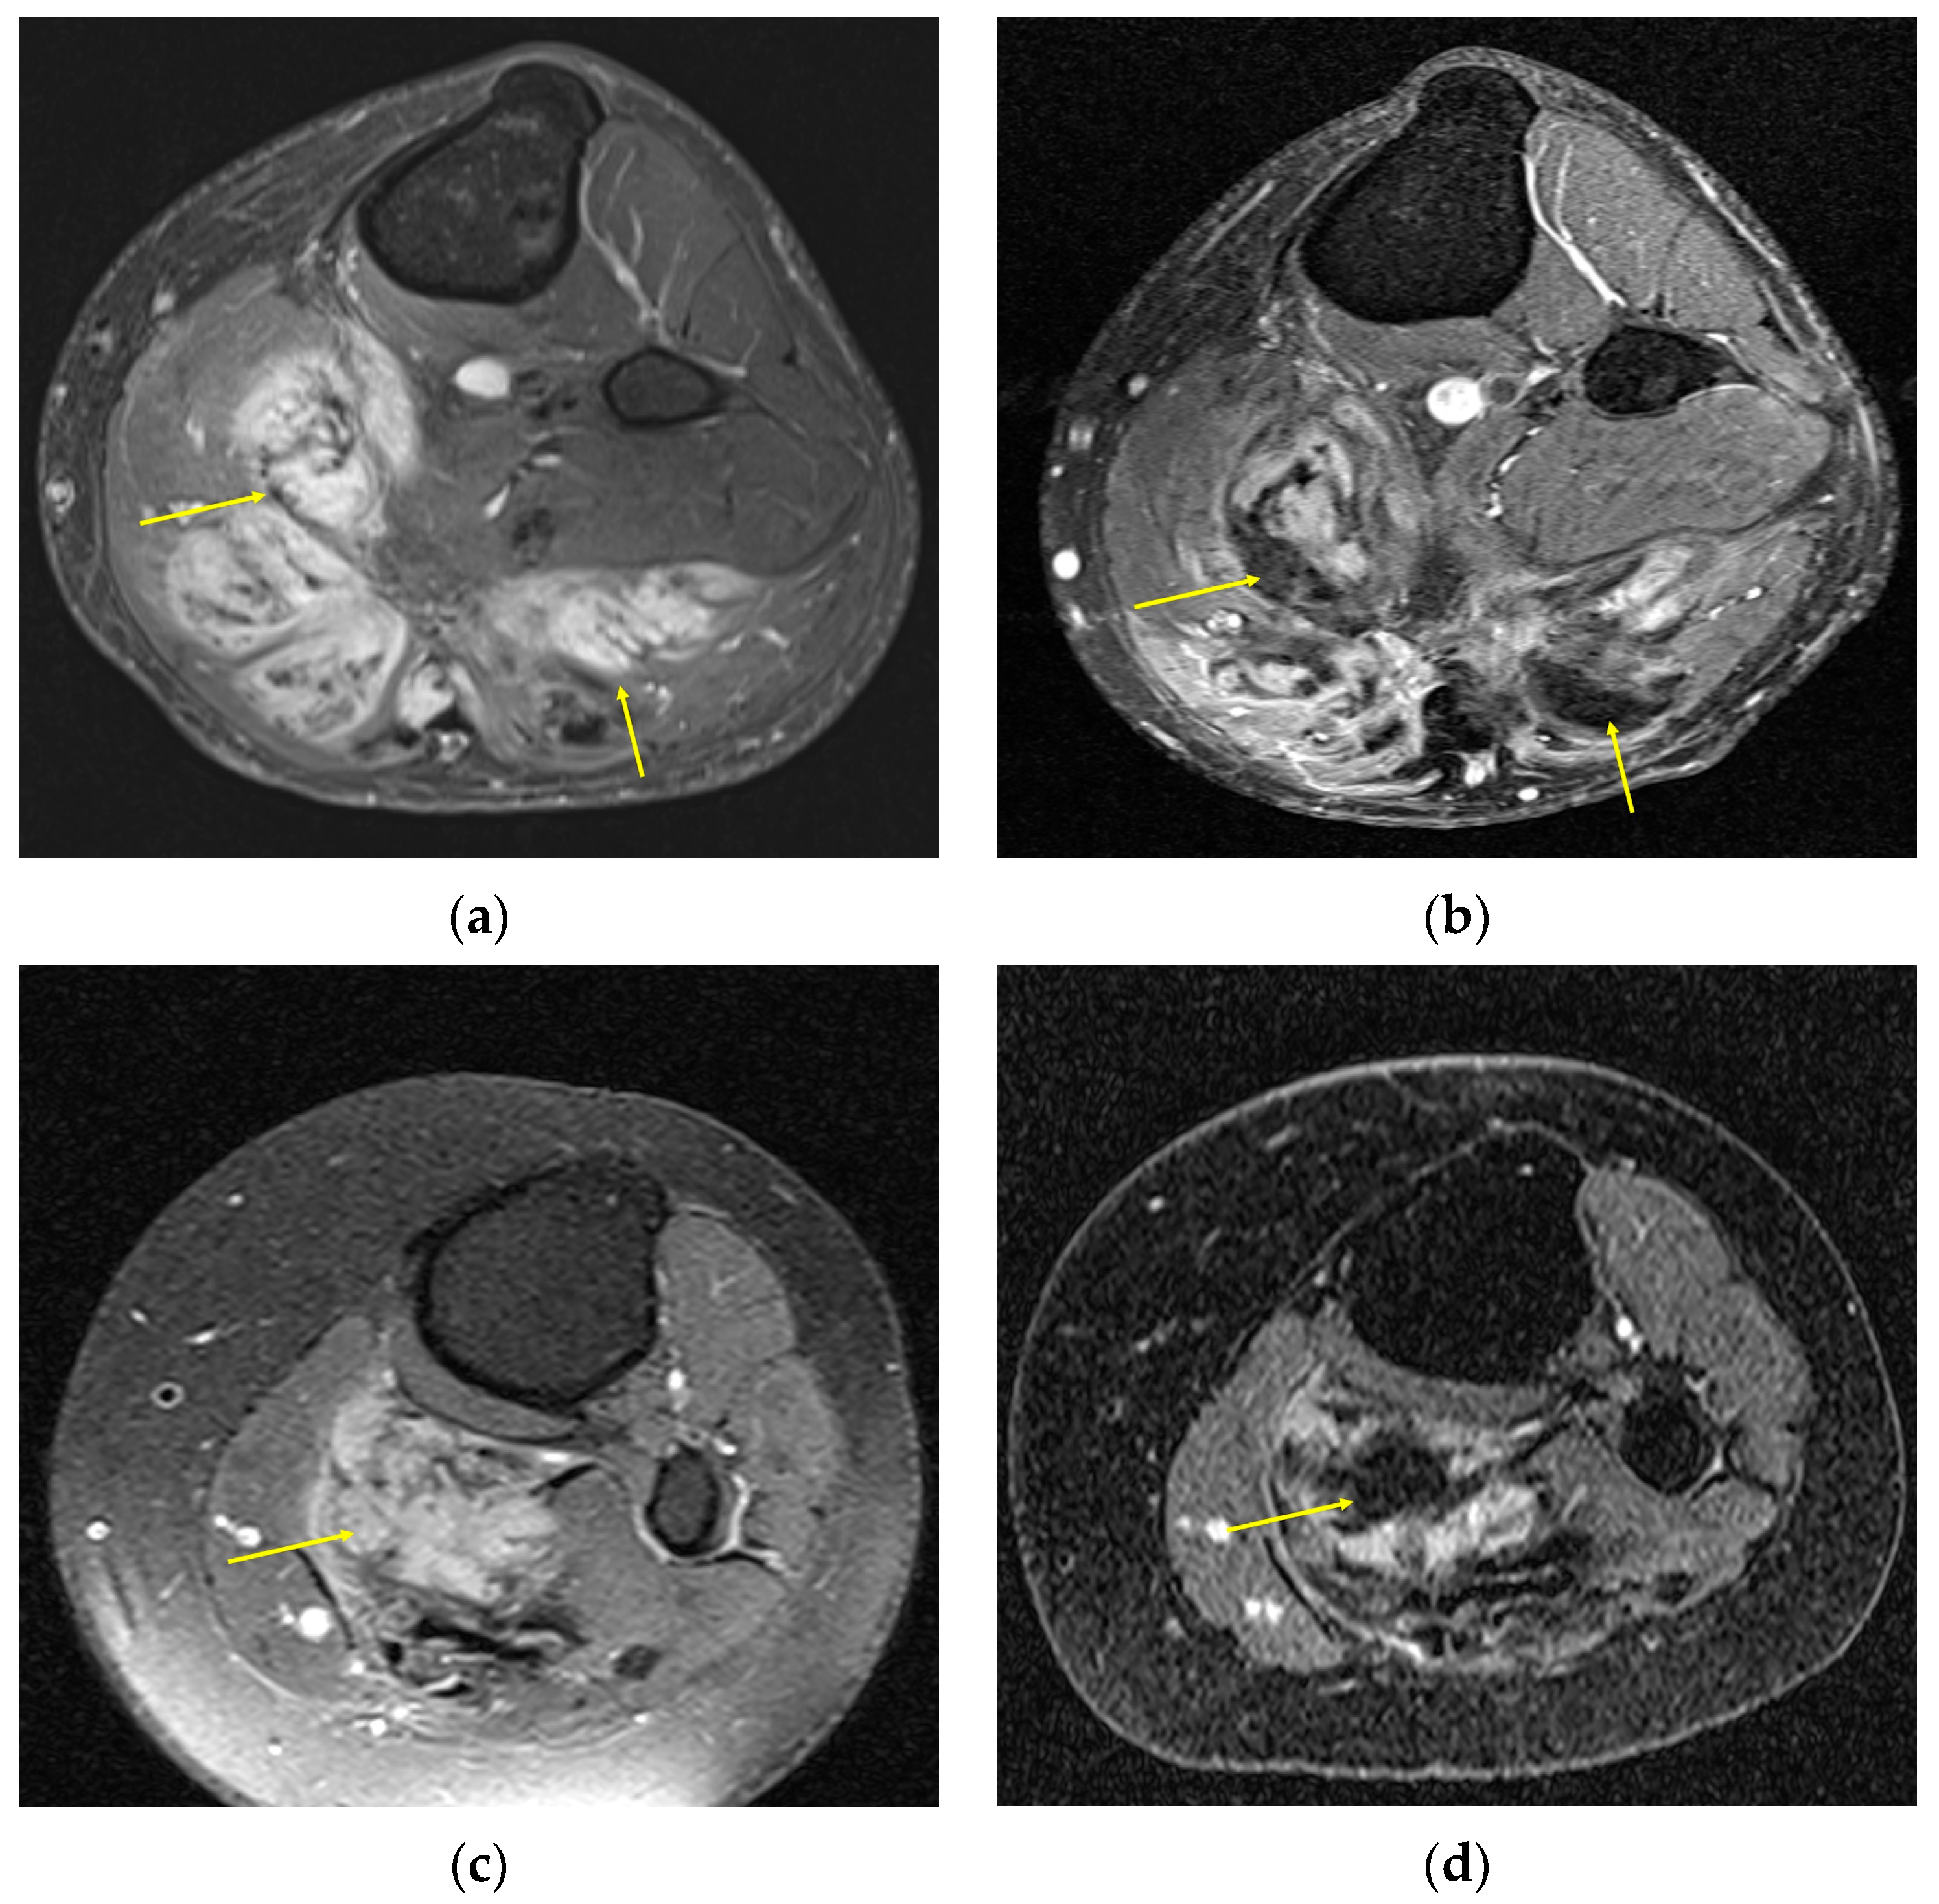

| MRI | Well-circumscribed, heterogenous with nonenhancing T1/T2 hypointense curvilinear areas related to collagen, and T1 intermediate to low/T2 intermediate to high areas related to cellularity or the myxoid matrix. Additional secondary signs (“flame”, “staghorn”, “fascial tail”, etc.) are described in text. |